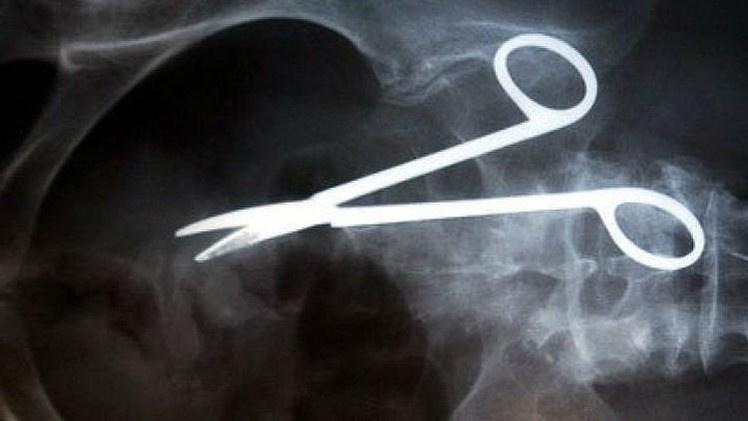

فقبل فترة قصيرة فقد هذا الشخص "53 سنة" الشهية تماما من جراء الألم وبدأ جسمه بالنحول، فقرر اجراء الفحوصات اللازمة لتشخيص السبب. من ضمن الفحوصات الطبية التي اجريت له كان التصوير بالأشعة السينية التي بينت وجود مقص طوله 20 سم في بطنه.

يقول احد الأطباء، "يبدو ان الجراح الذي اجرى العملية للمريض نسي المقص في بطنه، ويمكنني تصور الآلام التي كان هذا المريض يشعر بها طوال هذه الفترة". وبعد اجراء التحقيق تبين ان الجراح المذكور توفي قبل ثلاث سنوات.